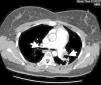

On return to the CCU, the patient experienced complete relief of chest pain and ST-segment normalization on the ECG. Nonetheless, her oxygen saturation level was still 90% despite high-flow oxygen by mask. A full transthoracic echocardiogram examination was then performed. A mass consistent with a thrombus was noted in the left atrium, appearing to arise from a redundant interatrial septum, while the right ventricle was moderately dilated with positive McConnell sign and the interventricular septum was displaced into the left ventricle, which was D-shaped in short-axis view (Figure 3). The pulmonary artery was dilated and the flow across the pulmonary valve suggested severe pulmonary hypertension with pulmonary artery systolic pressure estimated at 70 mmHg. In apical 4-chamber view, color flow imaging of the interatrial septum showed a right-to-left shunt. It was then decided to perform transesophageal echocardiography (TEE) to better characterize the relationship of the mass with the interatrial septum and its embolic potential, and also to look for masses in the right atrium. TTE showed a long thrombus that appeared to be attached to the atrial septum in the region of the foramen ovale. Color flow imaging was consistent with a patent foramen ovale (PFO) and the atrial septum was aneurysmatic. The thrombus had a snake-like movement inside the left atrium and its distal end was freely mobile, prolapsing through the mitral valve (Figure 4). No mass was observed in the right atrium or pulmonary arteries. Thoracic computed tomography angiography revealed bilateral thrombi in the main and lobar branches of the pulmonary artery (Figure 5).